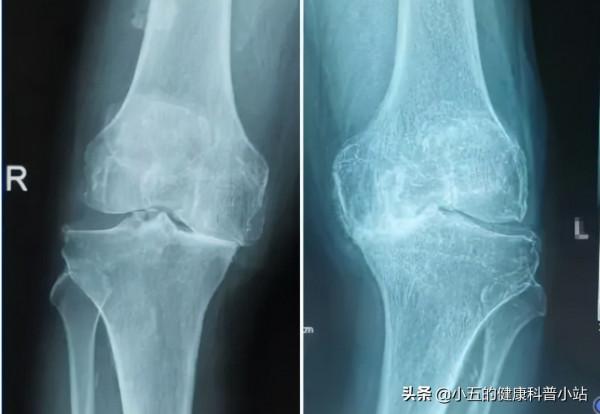

晚期的髕骨軟化症其實已經不僅僅侷限於髕軟骨了,而是整個膝關節的病理性變化,這時候膝關節無論動不動都會疼痛不適,並且一切活動都會出現明顯受限,這時候可以說膝關節已經完全喪失了正常的生理功能,同時伴有繼發性滑膜炎、關節積液。這時的影像學報告可見膝關節有明顯增生和狹窄,並且可伴有半月板、交叉韌帶的水腫和損傷。